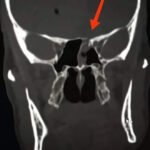

وأوضح مدير الهيئة الدكتور إسكندر عمار في تصريح لمراسلة سانا أنه تم قبول المريض ومتابعته في شعبة الجراحة العصبية، وبعد إجراء الاستقصاءات الشعاعية تبين وجود كسر قاعدة أمامية يسرى على مستوى الجدار الخلفي للجيب الجبهي ويمتد باتجاه الصفيحة الغربالية.

بدوره أوضح رئيس قسم أمراض الرأس والعنق وجراحتها الدكتور محمد خليل اختصاصي الأذنية أنها المرة الأولى التي تجرى فيها عملية نوعية بالتعاون بين الشعبة الأذنية والجراحة التنظيرية وشعبة الجراحة العصبية في المشفى، وذلك بعد تحديد مكان الكسور، ووضع خطة لمعالجتها ليتم التدخل تنظيرياً على منطقة النز والتدخل الخارجي على منطقة الكسر بالجدار الخلفي للصفيحة أو للجيب الجبهي.